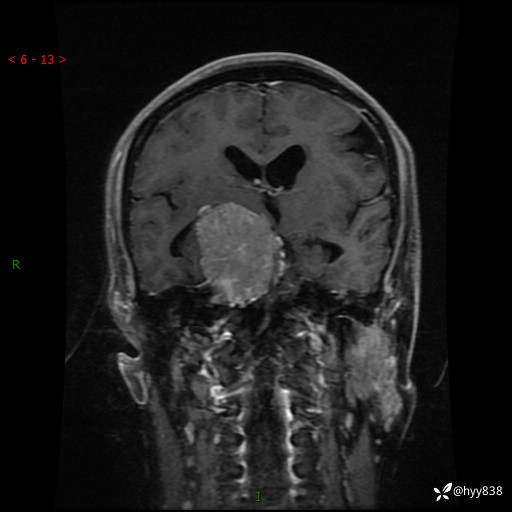

颅脑MRI平扫+增强